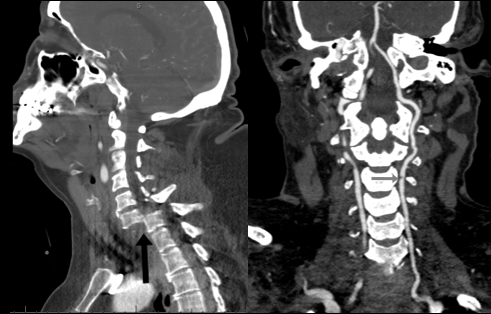

Diagnostic modalities covered in the training program include x-ray, ultrasound, computed tomography (CT), CT angiography, magnetic resonance imaging (MRI), MR angiography, fetal MRI, diffusion tensor imaging (DTI), functional MRI (fMRI), MR spectroscopy (MRS), and other advanced imaging techniques including CT and MR perfusion. Neuroendovascular procedures are performed in two state-of-the-art biplane angiography suites. Fellows have the elective opportunities to rotate in our active neuroendovascular surgery service with rotations also available in neurovascular ultrasound, anesthesiology pain management, and neuropathology.